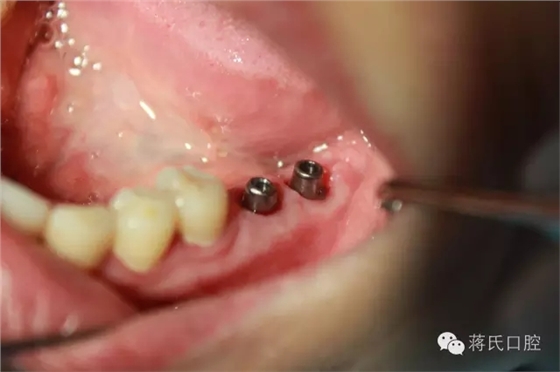

3.修復(fù)基臺以成品為主,優(yōu)點(diǎn)強(qiáng)度大,螺絲扣密和